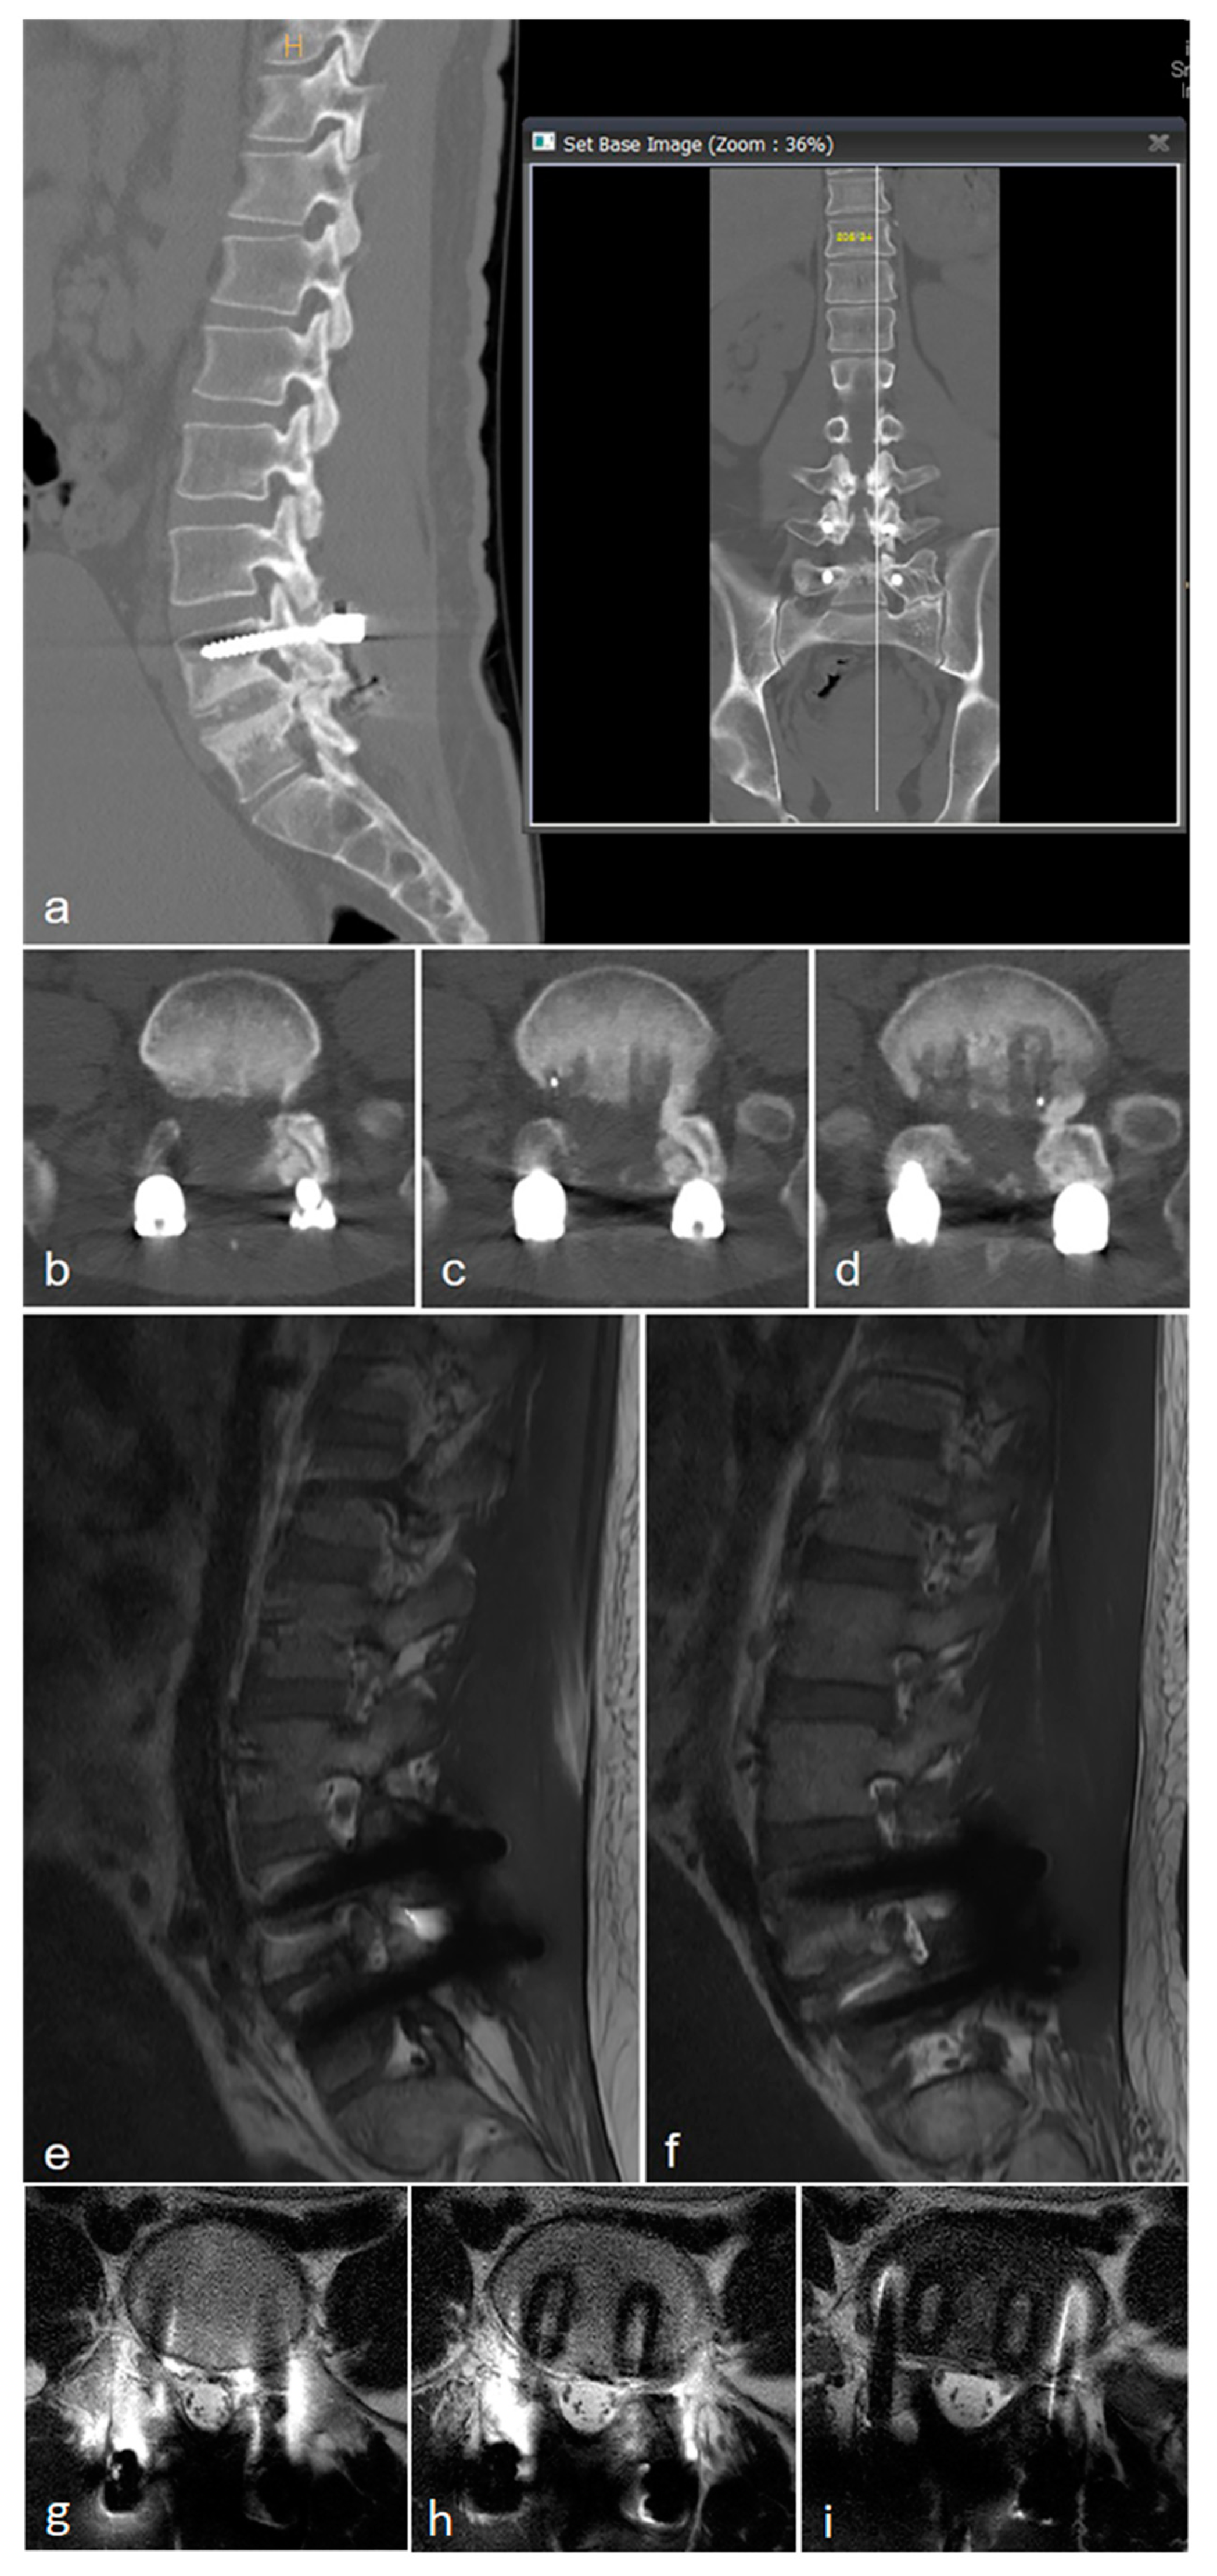

2.1. Case 1